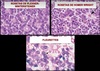

Quais são os achados fundoscópicos do Retinoblastoma?

- Lesão elevada, esbranquiçada

- Uni ou multifocal

- Vaso nutridor

- Calcificação da lesão

Quais são os padrões de crescimento do Retinoblastoma?

1. Endofítico

- sementes vítreas

- pseudo-hipópio (baixa mobilidade e irregular)

2. Exofítico:

- DR exsudativo

3. Infiltrado Difuso na Retina